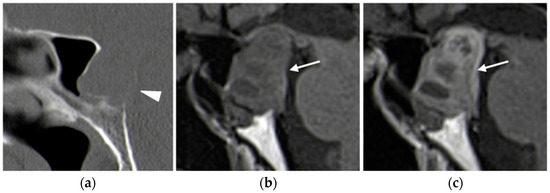

CT

- -

- Type A enhances more avidly than the thyroid in the arterial phase;

- Type B remains hypodense in both arterial and delayed phases;

- Type C shows less avid enhancement than the thyroid on both arterial and delayed phase images, with greater attenuation than the thyroid in the delayed phase [27].

- Bahl, M.; Sepahdari, A.R.; Sosa, J.A.; Hoang, J.K. Parathyroid Adenomas and Hyperplasia on Four-dimensional CT Scans: Three Patterns of Enhancement Relative to the Thyroid Gland Justify a Three-Phase Protocol. Radiology 2015, 277, 454–462. [Google Scholar] [CrossRef] [PubMed]

- Bunch, P.M.; Randolph, G.W.; Brooks, J.A.; George, V.; Cannon, J.; Kelly, H.R. Parathyroid 4D CT: What the Surgeon Wants to Know. Radiographics 2020, 40, 1383–1394. [Google Scholar] [CrossRef] [PubMed]